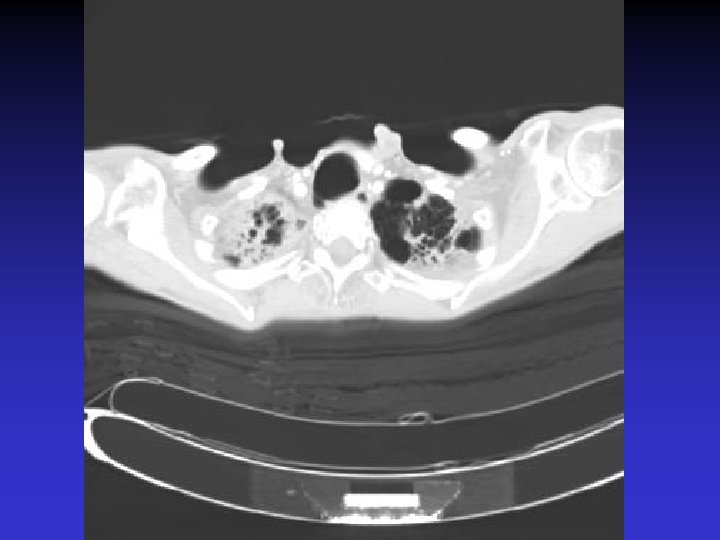

NTM lung disease n n MAC, M. kansasii, M. abscessus >50 years, ? M vs. F Symptoms n variable, nonspecific n chronic or reoccurring cough n sputum production, fatigue, malaise, dyspnea, fever, hemoptysis, chest pain, wt loss n more constitutional symptoms with advancing disease n evaluation complicated by sx of coexisting lung disease CXR n Fibrocavitary – often like MTB, but may be dense airspace dz or solitary cavity w/o cavitation n Nodular/bronchietatic – typical MAC, usu. mid-lower lung fields, +/- cavitation

M. simiae n n M. simiae may be confused with MTB as it is the only niacin-positive NTM Maoz et al. compared pts in Israel with M. simiae vs MTB. Pts with M. simiae: n More females, older age n Higher rates of smoking, COPD, other dz (DM, CAD, cancer), immunosuppressive drugs n Less HIV n Blunted symptoms n More noncavitary infiltrates in middle/lower lobes Most M. simiae isolates were contaminants Treatment with clarithromycin, ethambutol, rifabutin, and streptomycin (with modification for sensitivities)